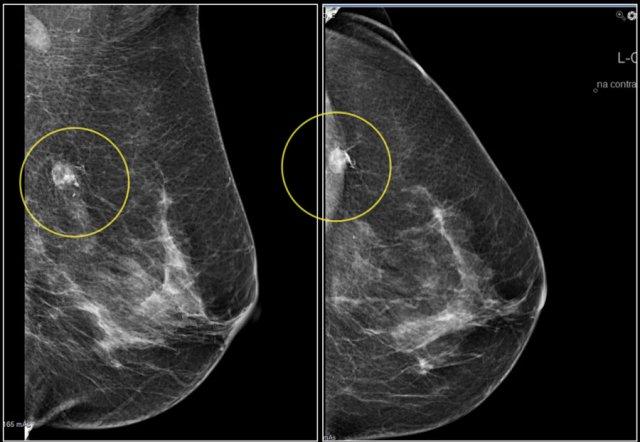

Lưu ý sự biến dạng cấu trúc vú bình thường trên tư thế chếch (vòng tròn vàng) và tư thế phóng đại.

Bệnh nhân đã được phẫu thuật cắt bỏ và chỉ tìm thấy mô sẹo trong bệnh phẩm.